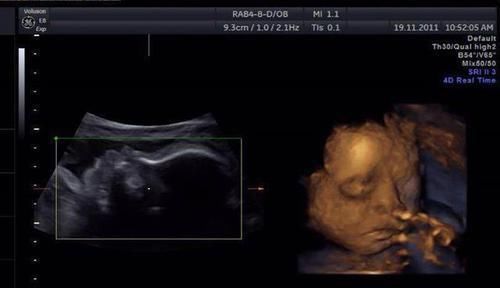

检测畸形儿的最重要方式是四维彩超,但千万不要把这项检查太过“神化”,它也不是万能的。

对此医院给出的解释是:四维彩超本就存在局限性,检出胎儿畸形率只有70%左右,而且检查准确性与多种因素有关,像这类手指畸形一般情况下是很难检查出来的。

四维彩超主要显示胎儿在子宫内的实时动态影像,方便医生进行全方位观察,若发现异常也能及时进行处理。

能检查出的畸形:

头面部,包括鼻子、嘴巴、唇部的畸形问题,并排除脑积水等大脑畸形;

全部内脏器官,包括心脏,肝脏,脾脏,肾脏和肠胃;

较为明显的四肢畸形;

脊柱排列是否整齐且连续,以排查脊柱裂的问题。

很难或不能查出的畸形:

视力、听力;

手指或脚趾上存在的畸形:若宝宝做四维彩超时手一直握拳或双脚被其他部位遮挡,便很难发现问题;

先天性心脏病。